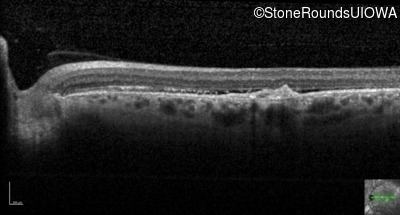

Optical Coherence Tomography - Right - 20/100

Exemplar / OCT Stack